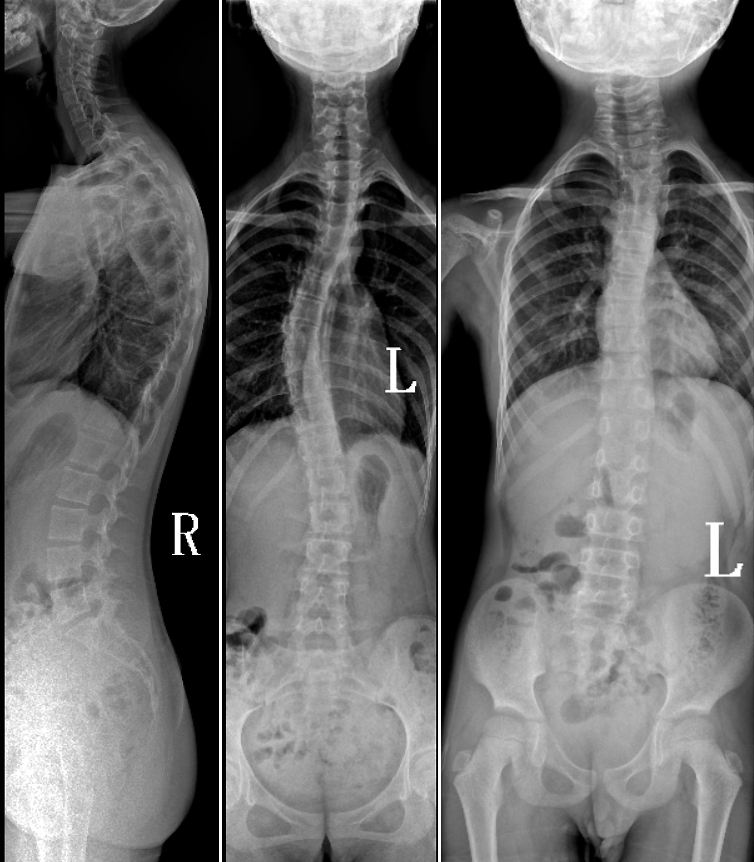

DR是臨床骨科的重要檢查手段之一。在骨科檢查中,脊柱矯形、長(zhǎng)骨骨折、腰椎退行性病變等,需要采集脊柱、下肢全景圖像,輔助醫(yī)生臨床診斷,從而制定科學(xué)的治療方案,普愛醫(yī)療的大視野平板動(dòng)態(tài)DR就像是一座橋梁,連接起現(xiàn)代醫(yī)療技術(shù)與當(dāng)?shù)厝嗣竦尼t(yī)療需求。

普愛醫(yī)療自主研發(fā)的大視野平板動(dòng)態(tài),采用17"*34"的有效視野,一次曝光即可得到全脊柱或全下肢影像。相較于多張攝影再軟件拼接的DR設(shè)備,PLX8600解決了拼接圖像存在密度不均勻,拼接處圖像配準(zhǔn)和放大效應(yīng)等問題,給臨床帶來了真正的大視野影像解決方案。